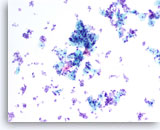

Lubricant B treated vial

…shows the effect of excessive lubricant.The field of view has sparse cellularity with an increase in the amount open spaces. In this instance, the excessive lubricant interfered with the cell collection process during slide preparation.

10x

Lubricant B treated vial

…shows the effect of excessive lubricant. The field of view has sparse cellularity with an increase in the amount open spaces. In this instance, the excessive lubricant interfered with the cell collection process during slide preparation.

10x